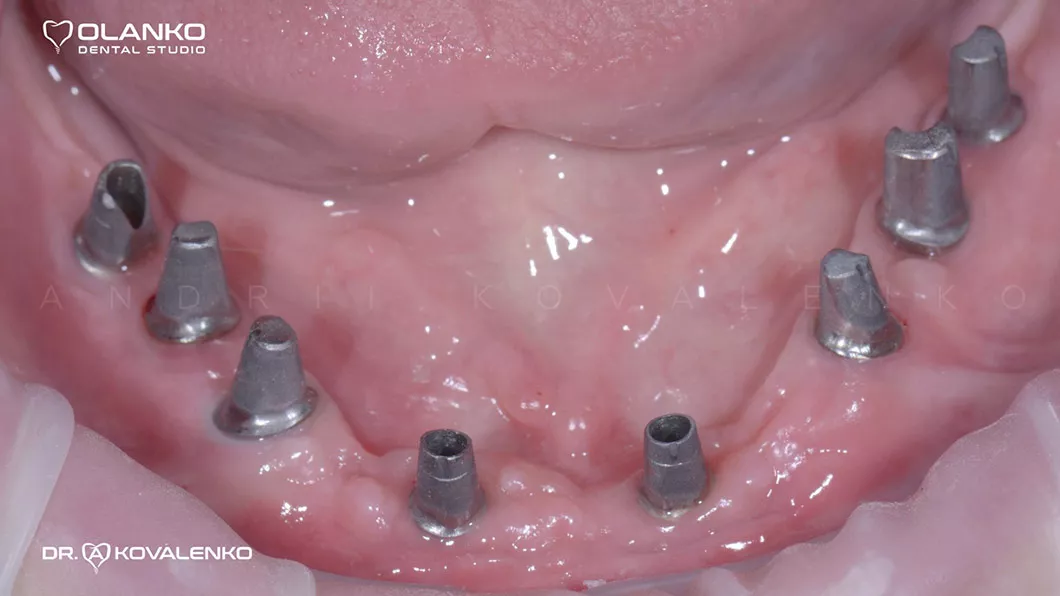

Вид в полости рта перед установкой керамических конструкций на имплантатах

Клинический случай 1 имплантация зубов